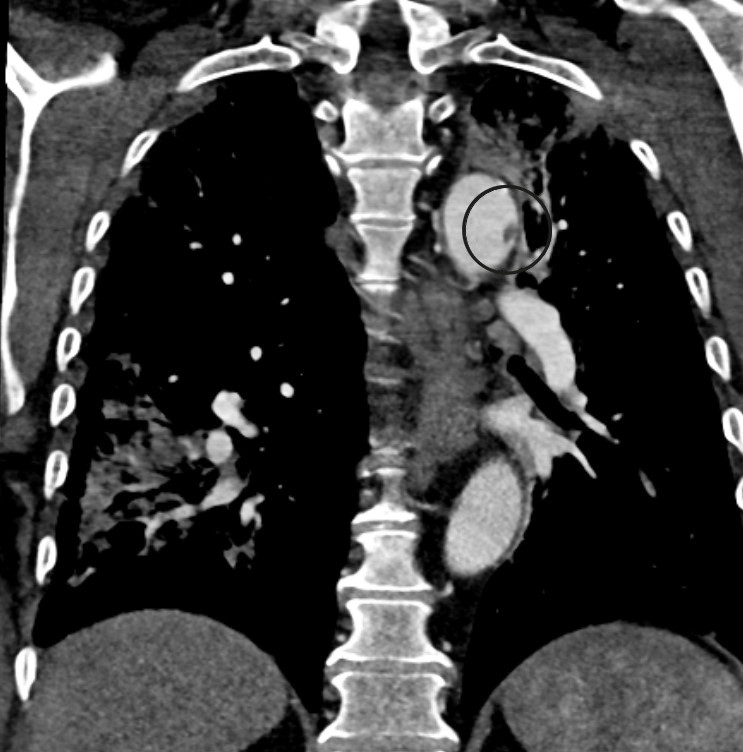

Postoperativt var det tilbakegang av alle symptomer i bena, men pasientens oksygenmetning var påfallende lav med SpO2 på 94,5 % (referanseområde > 99 %). Blodgass tatt mens pasienten fikk 3 L O2 via nesekateter viste pH 7,47 (7,36−7,44), pCO2 4,5 kPa (4,5−6,1) og pO2 8,9 kPa (> 9,6). Det ble utført CT toraks-angiografi, som viste flere lungeembolier i begge underlapper samt mattglassforandringer typiske for gjennomgått covid-19-pneumoni (figur 2). I tillegg så man en 7 mm stor pendulerende trombe distalt i aortabuen (figur 3). Dalteparin ble økt til 10 000 IE × 2, og pasienten fikk ikke-invasiv respirasjonsstøtte på intensivavdeling.

Ved ekkokardiografi to dager senere ble det påvist en trombe med diameter på 1 cm i apeks av hjertet. Det var lett apikal hypokinesi, men ellers god kontraktilitet av venstre ventrikkel. Det ble ikke påvist hjertearytmi eller tegn til gjennomgått hjerteinfarkt. En hematologisk utredning, med tanke på antifosfolipid syndrom (inkludert testing av lupus antikoagulant, anti-cardiolipin-antistoffer og beta-2 glycoprotein I antistoff) viste ingen patologiske funn som kunne forklare embolisering. Normale trombocytter og lett forhøyet fibrinogen på 5,3 g/L (1,9–4) og D-dimer på 14,8 mg/L (< 0,57) var som forventet ved trombose. Man konkluderte med at pasienten var tilstrekkelig behandlet med dalteparin 10 000 E × 2, at pasienten skulle følges opp av hematolog og etter hvert skifte behandling til DOAK eller marevan. Ni dager etter innkomst ble pasienten skrevet ut i velbefinnende med normal gangfunksjon. Han ble henvist til videre oppfølging ved medisinsk avdeling på lokalsykehuset.